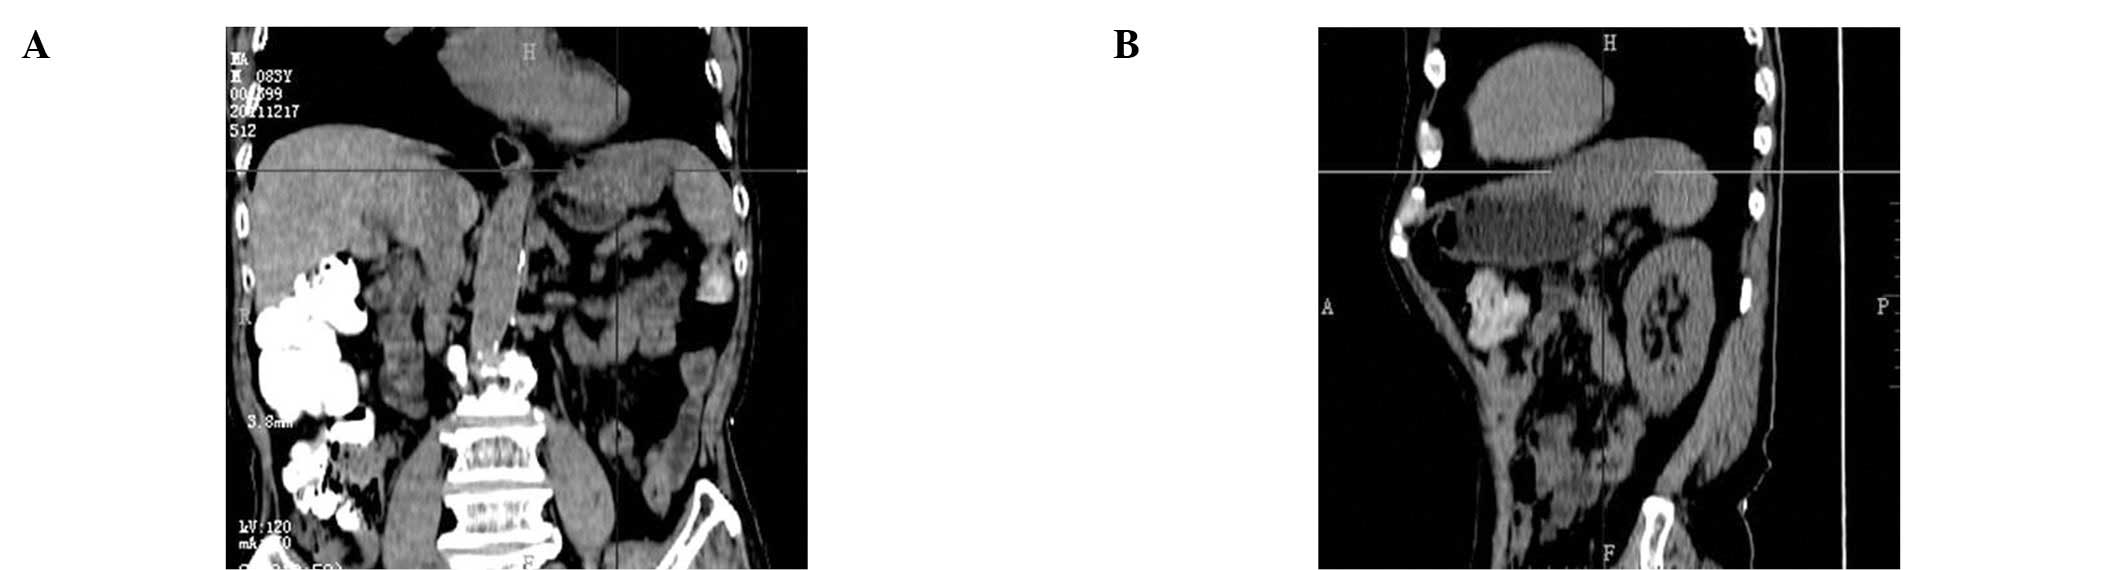

A computed tomography (CT) scan with intravenous

contrast medium revealed a heterogeneous mass, with a maximum

diameter of 8.3 cm and a density of −24 to 35 HU, located between

the stomach and spleen (Fig. 1A and

B). A positron emission tomography-computed tomography (PET/CT)

scan also revealed a lesion with an uneven, rim-shaped pattern,

rather than a global fludeoxyglucose (18F; FDG)-uptake

pattern (Fig. 2A–C). The abdominal

CT screen obtained prior to the GIST resection was reviewed and

revealed a homogeneous lesion measuring ∼4×4 cm and invading the

stomach wall (Fig. 3).